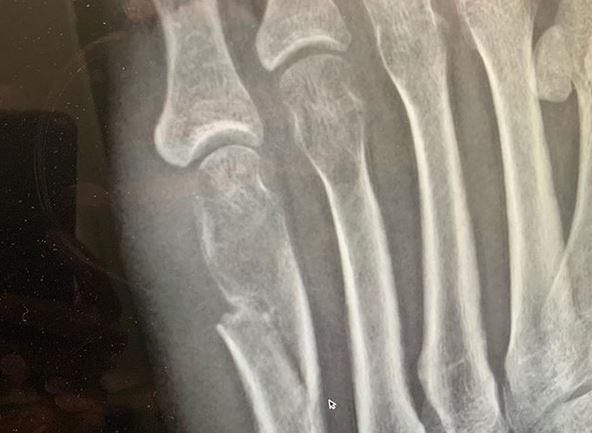

Ok, let's start from the beginning. I broke my foot. Not a fracture, not a sprain, I broke it all the way. My break is just below my left pinky toe. How did I do it, you ask? No surprise, doing something stupid. Dancing. Yes, dancing.

You can see where this is headed. I did one giant, albeit angelic leap into the air, but did not stick the landing. Instead, my dumb foot got caught up in my dumb flip flop and crunch! I fell to the floor immediately. I could hear it on impact. I knew immediately it was broken. So, I hobbled on our and drove myself the the ER, where they all confirmed my idiocracy.

Fast forward to 13 weeks later. I am still broken and in a boot. Why? Apparently, when you're old (37) your bones don't heal as quickly. Yay! Not only that, but where I broke it, is one of the hardest places to heal. By the way, the doc also put me on a bone stimulator which is supposed to help it grow faster and stronger. So far, he can't tell if it's working. Yay!